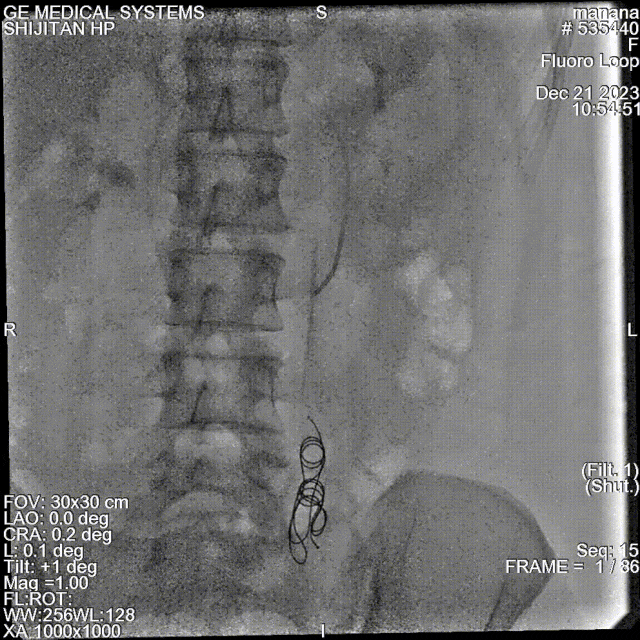

★ 卵巢静脉造影(诊断金标准)

尽管是侵入性操作,但静脉造影仍是诊断的“金标准”。其诊断标准(2019UIP)包括:

卵巢静脉直径 > 6 mm;

造影剂在盆腔静脉丛滞留 > 20秒;

盆腔静脉丛充血、迂曲,造影剂反流可越过中线;

可见同侧或对侧髂内静脉、外阴、阴道及大腿静脉曲张显影。

反流性疾病:卵巢静脉和/或髂内静脉反流——建议行卵巢静脉栓塞(Ⅱa B级推荐)。但需注意,部分患者合并髂内静脉反流,需一并处理。